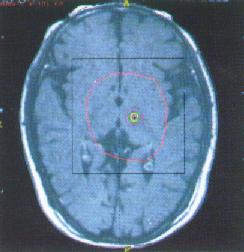

②腦深部電刺激:刺激靶點主要是丘腦底核和蒼白球,原理是糾正基底節過高德意志性輸出以改善症狀;使適用於藥物治療失效、不能你受或出現異動症狀者,對年齡較輕,症狀以震顫、強直為主且偏於一側者效果較好,術後仍需藥物治療;